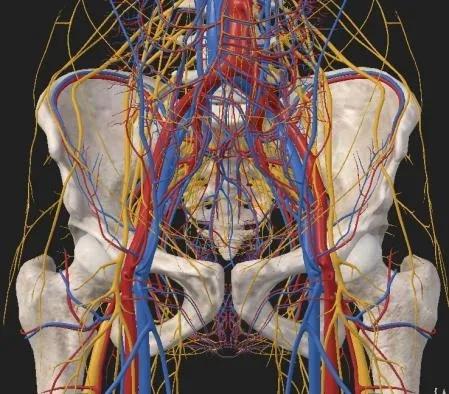

髋臼,作为连接躯干与下肢的“承重碗”,其解剖结构复杂、生物力学关键,直接决定着人体负重、行走与平衡功能。复杂髋臼骨折因其位置深在、骨折类型多变、毗邻重要神经血管结构,长期以来被视为创伤骨科领域最具挑战性的手术。

▲髋臼周围血管神经分布

随着现代精准外科理念的深入与微创技术的飞速发展,这一传统模式已发生颠覆性变化。玉林市中西医结合骨科医院骨盆科于2017年初系统开展髋臼前方新型入路——腹直肌外侧入路(LRA),该方式切口小,由盆腔经神经血管间隙入路,避免了大量的组织离断,出血少,损伤小;但技术要求高,对局部解剖要非常熟识,学习曲线长。骨盆科团队历经多年临床实践与技术优化,已将此技术熟练掌握并全面纳入复杂髋臼骨折治疗的常规路径;LRA入路具有手术切口5-8厘米的小切口、精准的解剖间隙进入分离显露、术野清晰、出血少、软组织损伤程度低等优势,此技术显著提升了手术安全性及降低术后的并发症。目前,我院骨盆科团队已累计完成三百余例LRA微创手术,积累了丰富的临床经验,正引领复杂髋臼骨折治疗迈向创伤更小、精度更高、恢复更快的“微创时代”。